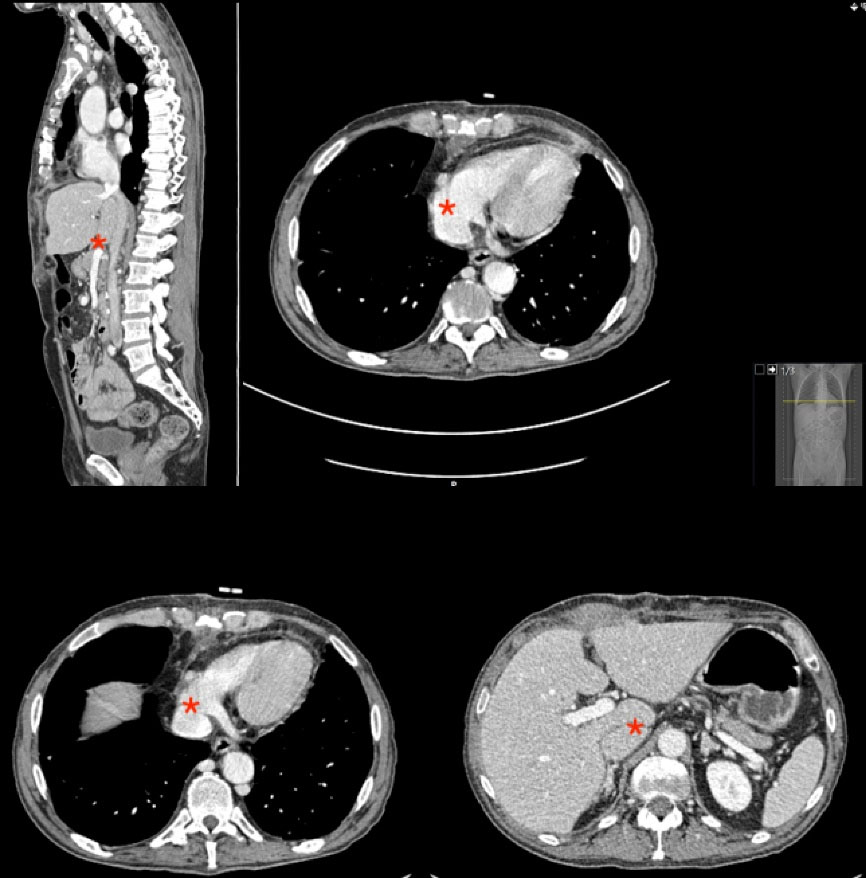

Below we describe the tumor thrombectomy technique according to the intervention performed on patient 4. The intervention consisted of ultrasound-guided puncture of the left common femoral vein and insertion of a 7Fr introducer sheath. Through a laparotomy, the intestines were oriented to dissect the peritoneum and expose the retroperitoneal space. Standard nephrectomy was performed without ligation of the corresponding renal vein. Using the Pringle maneuver, the liver was mobilized to release the retrohepatic vena cava. After median sternotomy and systemic heparinization we performed for cannulation of the superior vena cava (SVC), common femoral vein (CFV) and brachiocephalic trunk (BCT), and started ECC. Figure 2 shows the incisions used to perform the intervention. The SVC was excluded and a right atriotomy was performed. Figure 3 shows the proximal portion of the tumor thrombus in the right atrium. In turn, the IVC was opened and a thrombectomy was performed, in a caudal direction to the right atrium, extracting the piece en bloc. Figure 4 shows the IVC with the thrombus inside.

Figure 3.

Proximal portion of the tumor thrombus in the right atrium